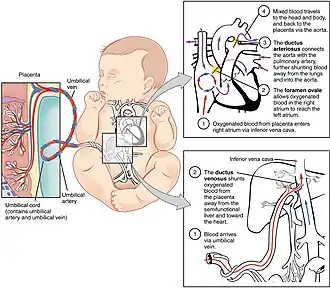

In humans, the circulatory system is different before and after birth. The fetal circulation is composed of the placenta, umbilical blood vessels encapsulated by the umbilical cord, heart and systemic blood vessels. A major difference between the fetal circulation and postnatal circulation is that the lungs are not used during the fetal stage resulting in the presence of shunts to move oxygenated blood and nutrients from the placenta to the fetal tissue. At birth, the start of breathing and the severance of the umbilical cord prompt various changes that quickly transform fetal circulation into postnatal circulation.[1][2]

The placenta functions as the exchange site of nutrients and wastes between the maternal and fetal circulation.[3] Water, glucose, amino acids, vitamins, and inorganic salts freely diffuse across the placenta along with oxygen. Two umbilical arteries carry systemic arterial blood from the fetus to the placenta where waste is exchanged for oxygen and nutrients. The oxygenated blood will then return to the fetus from the placenta via the umbilical vein.

Oxygenated blood from the placenta is carried to the fetus by the umbilical vein, which will drain into the inferior vena cava (IVC) through the ductus venosus or the liver.[5] When oxygenated blood enters the IVC, it moves in parallel with deoxygenated blood from the fetal systemic veins, establishing a bilaminar blood flow as it enters the right atrium.[2]

The fetal heart contains two upper atria and two lower ventricles. It also contains two additional structures, the foramen ovale and the ductus arteriosus, that function as shunts for oxygenated blood.[2] The function of these shunts is to bypass the lungs and maintain proper circulation to important fetal tissue. In the fetal stage, the lungs fill with fluid and collapse because the fetus is within the amniotic sac and the placenta is providing the oxygen it needs to grow. With the lung collapsed, pulmonary vascular resistance remains high during the fetal stage to prevent blood flow into the lungs.[2] As oxygenated blood arrives at the right atrium, the eustachian valve helps direct the oxygenated blood into the foramen ovale, an opening between the right and left atrium. As the blood flows through the left atrium, it will move through the mitral valve into the left ventricle and will be pumped through the aorta into the body. The shunting of oxygenated blood from right to left atrium will supply blood high in oxygen and nutrient content to the upper extremities, including the critically important brain. Some of the blood moves from the aorta through the internal iliac arteries to the umbilical arteries, and re-enters the placenta, where carbon dioxide and other waste products from the fetus are taken up and enter the maternal circulation.[1][2]

Some of the blood entering the right atrium does not pass directly to the left atrium through the foramen ovale, but enters the right ventricle. This blood consists of oxygenated placental blood and deoxygenated blood returning from the fetal circulation.[2] This blood is pumped into the pulmonary artery. At the pulmonary artery, it is met with high pulmonary vascular resistance as a result of collapsed lungs and pulmonary capillaries. In the fetus, there is a special connection between the pulmonary artery and the aorta, called the ductus arteriosus.[2] Because the aorta has lower pressure than the pulmonary artery, most of the blood flows across the ductus arteriosus away from the lungs.[1] Once the blood goes through the ductus arteriosus, it mixes with the blood from the aorta. This results in mixed blood oxygen saturation that supplies most of the structures of the lower half of the fetal body.[6]